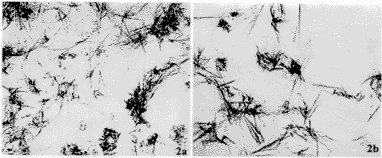

神经元存活力是通过测定MTT在线粒体脱氢酶代谢过程中形成的有色产物的A值来评价,A值高反映了神经元存活力强,存活数量多。MTT法测量结果显示:Aβ31-35和ApoE4单独作用各组测定的A值与对照组比较无明显差异。Aβ31-35(10μmol/L)+ApoE4(10μmol/L)和Aβ31-35(20μmol/L)+ApoE4(10mg/L)两组测得的A值分别为0.172±0.021,0.155±0.014,比对照组(0.208±0.018)低,有显著差异(P<0.05),说明Aβ31-35+ApoE4对基底前脑神经元存活有抑制作用(图1,2a,2b)。

图2 基底前脑神经元培养48h时,对照组(图2a)和Aβ31-35(20μmol/L)+ApoE4(10mg/L)组(图2b)神经元MTT阳性反应产物的比较,图2b中神经元MTT阳性反应产物比图2a多。倒置相差显微镜 ×200

Fig.2 Showing MTT positive products of the basal forebrain neurons in cultures after treated with Aβ31-35 and ApoE4 for 48h.a,control;b,group Aβ31-35+ApoE4.MTT positive products of neurons in normal control are richer than those of group Aβ31-35+ApoE4 phase-contrast microscopy. ×200